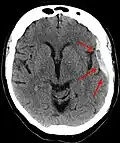

Le diagnostic se fait au scanner sans injection. Son accès est facile dans les pays développés. Il n'existe pas de contre-indication (sauf la grossesse).

Sur le scanner crânien, fait sans injection de produit de contraste, l'hématome sous-dural se présente habituellement sous une forme de croissant, dont la concavité suit la courbe du cerveau, stoppé seulement par les réflexions durales telles que la faux du cerveau et le tentorium. Cependant ils peuvent avoir une forme convexe, spécialement tout au début du saignement, ce qui peut les faire confondre avec les hémorragies épidurales (hématome extradural). Le sang peut être vu comme une densité stratifiée tout au long du tentorium. Dans les cas chroniques, on peut voir l'effacement des sillons ou le déplacement médian de la jonction substance blanche/substance grise, mais le sang peut avoir une densité très proche de celle du tissu cérébral (isodense), ce qui peut masquer l'hématome.

Les hématomes sous-duraux sont plus fréquents dans les parties supérieure et latérales du frontal et au niveau des lobes pariétaux[5],[12] ainsi que dans la fosse postérieure proche de la faux du cerveau et de la tente du cervelet[5].